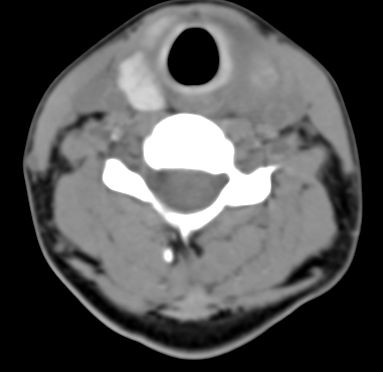

标题: CT9717:F、30Y、颈部左侧包块半年,压痛.患者拒绝作增强。 [打印本页]

标题: CT9717:F、30Y、颈部左侧包块半年,压痛.患者拒绝作增强。

请各位老师帮忙看看左侧甲状腺病灶!

左侧甲状腺增大,密度降低,性质不好定,还是作个增强,或作核素扫描.

甲状腺弥漫增大,以左叶明显,内见不均匀低密度影,边缘模糊欠清,周围脂肪间隙模糊。

结合病史:考虑亚急性甲状腺炎可能性大。(不知道病人有没有检测tsh t3 t4)

左侧甲状腺及甲状腺狭部弥漫性增大,边缘模糊,未见明确界线.考虑甲状腺炎可能性大.

左侧甲状腺弥满性增大,其内密度均匀减低,气管无受压。周围结构清晰。考虑甲状腺炎可能性大。

甲状腺弥漫增大,以左叶明显,左侧内见不均匀低密度影,边缘模糊欠清,周围脂肪间隙模糊。